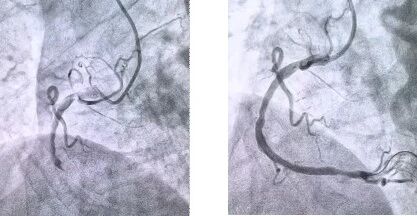

患者抵達(dá)醫(yī)院后,簡(jiǎn)化掛號(hào)、繳費(fèi)等中間環(huán)節(jié),迅速溝通病情,需要緊急介入治療,獲得家屬同意,立即送至導(dǎo)管室。造影顯示其右冠狀動(dòng)脈中段完全閉塞,醫(yī)生迅速實(shí)施血栓抽吸,球囊擴(kuò)張和藥物洗脫支架植入術(shù)。36 分鐘后,閉塞血管恢復(fù)正常血流,吳大爺?shù)难獕骸⑿穆手饾u平穩(wěn),胸痛癥狀明顯緩解。術(shù)后三天,他便轉(zhuǎn)入普通病房進(jìn)行康復(fù)訓(xùn)練,重拾健康生活。